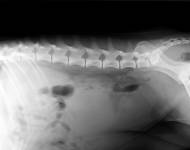

MVDr. Meloun: Lumbosakrální přechodový obratel